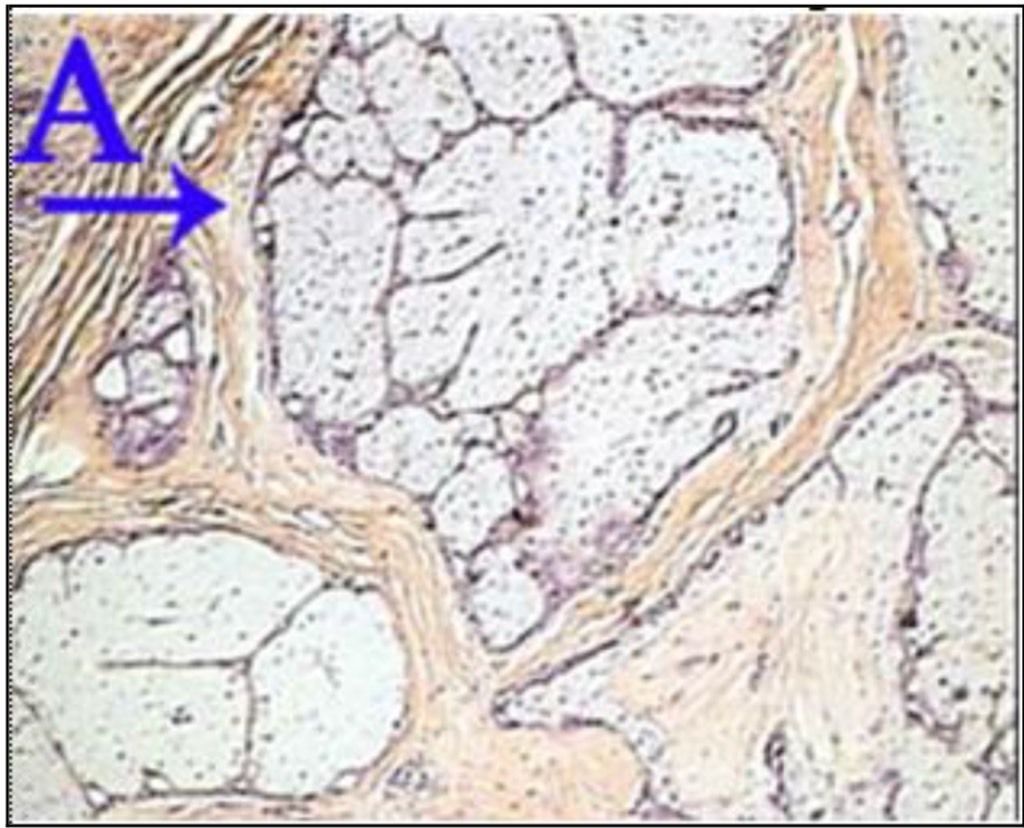

Question 21

Question

What is the correct answer at point A?

Answer

• - travée conjonctive

• - capsule

• - lobule

• - capillaire sanguin

• - adipocyte

Question 22

What is the correct answer at point B?

Question 23

What is the correct answer at point C?

• - lobule d’adipocyte

Question 24

What is the correct answer at point D?

Question 25

What is the correct answer at point E?